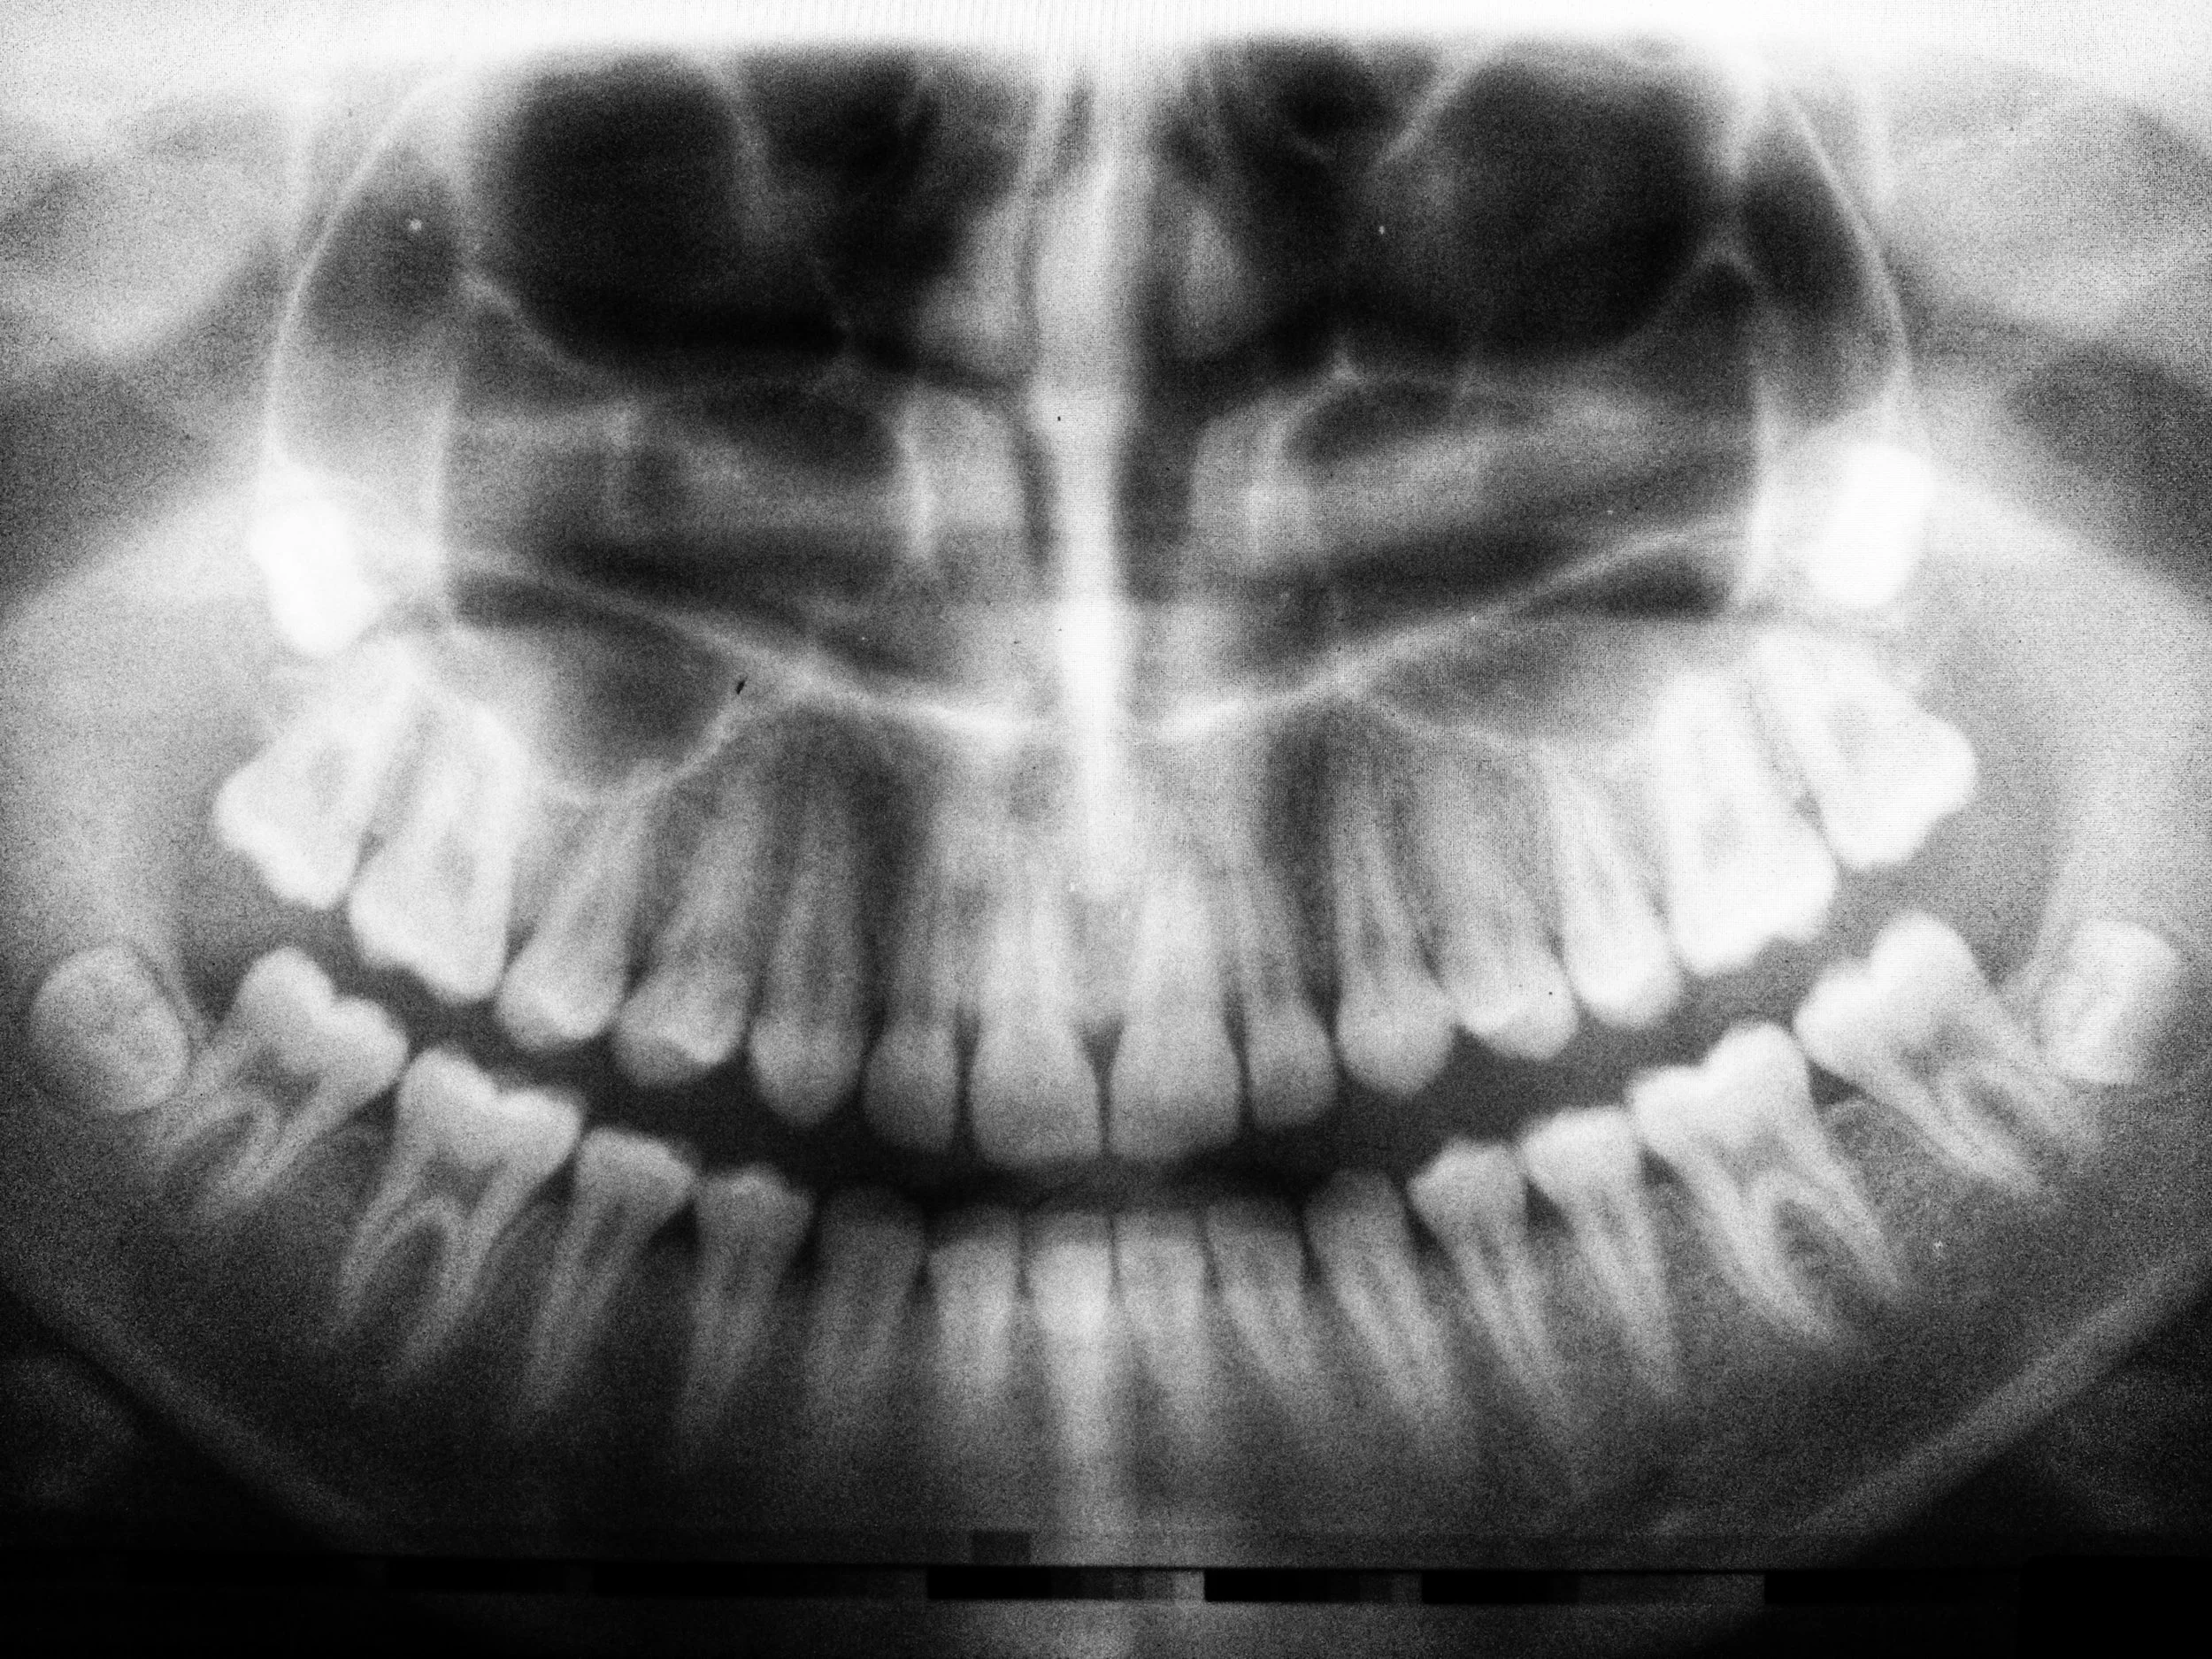

Wisdom teeth are the third set of molars at the very back of our mouths. In most cases, there are four of these ‘extra teeth’ (one on each corner of the jaw), but not everyone has them. The extra teeth appear in adults between the ages of seventeen and twenty-five but your dentist can spot them in an X-Ray before then.

Below, and to the right, is an Archer Dental patient with a perfect smile. All of his teeth are clean and straight and his mouth is big enough to comfortably accommodate all four wisdom teeth. This is what a full mouth looks like.